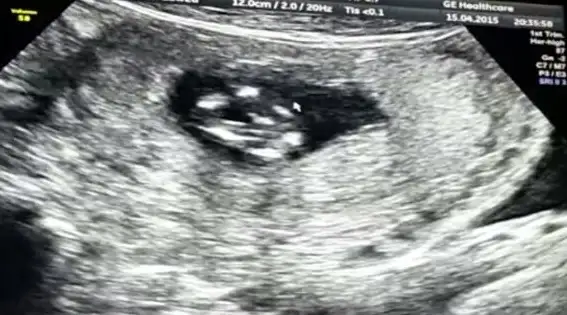

Bir önceki ultrason görüntüsünde bazı arkadaşlarımız bacak mı, pipi mi diye kararsız kalmıştı, bazı arkadaşlarımız kız demişti. Doktorum da kız demişti.

Bugün tekrar doktordaydım ve videoya aldık ultrason anımızı. Eve geldikten sonra çektiğimiz videoyu izledim. Doktor çok büyük ihtimalle erkek demeden hemen evvel ekranda bu görüntü var.:KK68: Sanırsam bacak arası ve pipisi de orada :KK48: O kadar büyük olur mu pipisi :KK48:

Anaaa :)) bebis erkegim diyoo annesiii doktoe hicmi bisey demedi bariz pipi ortada.. Sen böyle demişsin canım. Tebrikler valla resmen pipi ortadaymış :KK48:

Valla doktorda fark etmemiştim ama gelince gördüm ben de. Baya açmış. Bir de uyuyordu o zaman. Eminim doktorda beklemiyordu. Çünkü cinsiyet sordum, 16.haftada dedi. Sonra anlatmaya başladı işte, burası burnu, çene kemiği, burası alnı, bak elleri dedi. En son bacakları diyor ve sessizlik oluyor :KK48: Peşinden de çok büyük ihtimal erkek diyor :KK48: